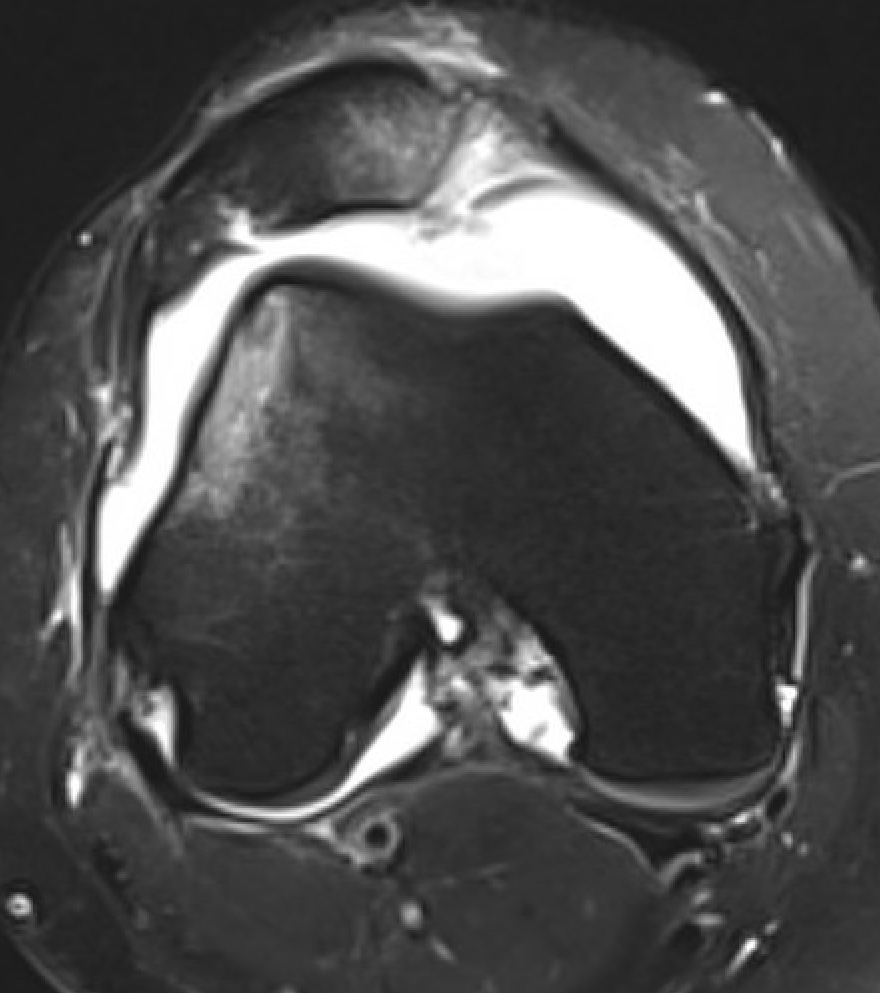

MRI

Advantage

- identify smaller chondral lesions

- identify size of osteochondral fragment better than CT

- diagnose MPFL tear location

Small chondral fracture in notch from medial facet patella, and avulsion of MPFL from patella

Large chondral fracture from medial facet of patella

Osteochondral fracture lateral femoral condyle